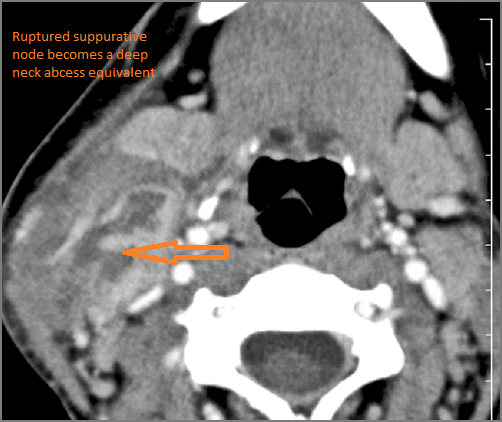

Cervical Lymph Nodes

There is suppurative cervical lymphadenopathy. [Yes/No]

If there is suppurative cervical adenopathy the purulent material outside the lymph node(s) capsule(s). [Yes/No]

Suppurative lymphadenitis